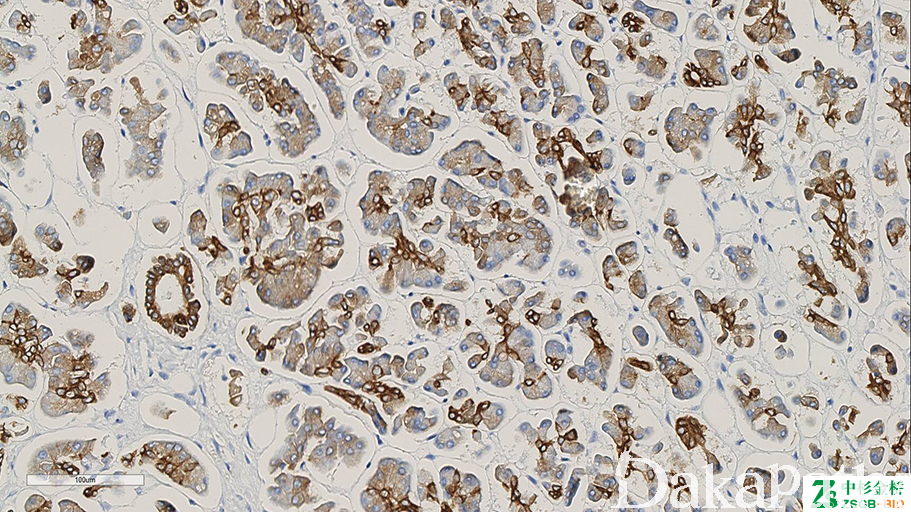

细胞角蛋白,能识别所有已知的碱性(II 型)细胞角蛋白。

信号定位: 胞质

肿瘤上皮性分化的标记之一。

在肿瘤中的表达情况:

几乎全部阳性(≥95%的病例阳性): 肺鳞状细胞癌、膀胱透明细胞癌、毛发上皮瘤、肾上腺嗜酸细胞性肾上腺皮质肿瘤、脑膜瘤,分泌性、食管基底样鳞状细胞癌、肾源性腺瘤

通常阳性(<95%,≥75%的病例阳性): 涎腺导管腺癌、涎腺玻璃样变透明细胞癌、肺腺癌

经常阳性(<75%,≥55%的病例阳性): 骨纤维结构不良、造釉细胞瘤、胆管癌

有时阳性(<55%,≥35%的病例阳性): 乳腺浸润性癌,非特殊类型、胃腺癌、鼻咽癌,非角化性、胰腺导管腺癌

少数阳性(<35%,≥15%的病例阳性): 肝细胞癌、非典型性脑膜瘤、鼻咽未分化癌

偶尔阳性(<15%,≥5%的病例阳性): 脑膜瘤,砂粒体型、脑膜瘤,横纹肌样、脑膜瘤,纤维型、脑膜瘤,移行型

几乎全部阴性(<5%的病例阳性): 肾细胞癌伴 Xp11.2 异位、黏液性软骨肉瘤、脑膜瘤,微囊性